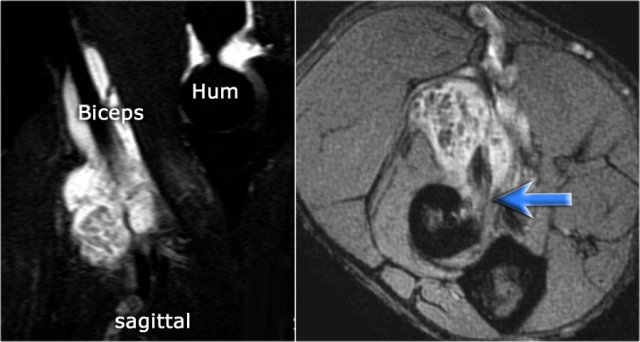

Typically the radiocapitellar joint is punctured from lateral with the patient prone and the arm flexed 90 degrees overhead (red arrow).

This however can sometimes cause problems if you are interested in the lateral ligaments and you inject lidocaine or contrast into these ligaments.

So more recently we started to use the posterior approach into the olecranon fossa (blue arrow).

Diluted gadolinium is injected, i.e. 0,05cc + 10cc saline (an "off-label" use in the US).

Continue with the axial scan.

As we look on the axial scan, we can appreciate the huge osteophyte formation.

Notice that the ulnar nerve (blue arrow) is next to these osteophytes and these patients may present with ulnar neuropathy.